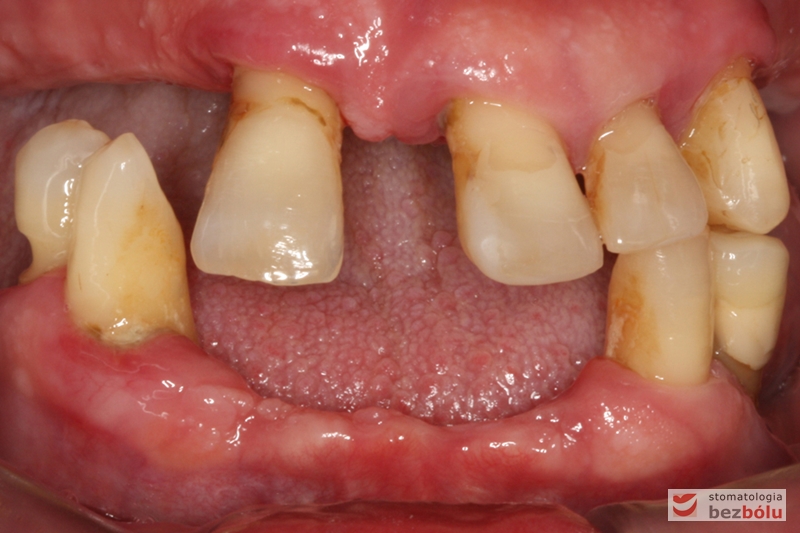

Stan wyjściowy - bez protez, liczne braki zębowe i po 2 nierokujące zęby w szczęce i żuchwie

Stan wyjściowy – bez protez, liczne braki zębowe i po 2 nierokujące zęby w szczęce i żuchwie